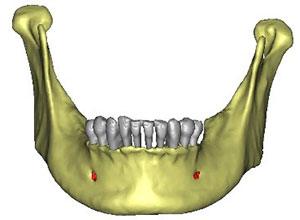

Este procedimiento requiere, en primer lugar, que tomemos los registros de la boca del paciente a través de una tomografía cone beam la cual se transfiere a el software que se encarga de proyectar la prótesis a través de la reproducción digital en 3D y obtener el mejor diagnóstico.

En el mismo software se realiza la planificación para la colocación de los implantes colocando virtualmente los implantes en la zona favorable y de esta manera se realiza una guía quirúrgica.